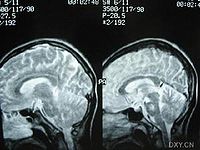

2.超声心动图对于药源性心包疾病、心肌病及心功能判断有帮助。

3.放射性核素心脏显像对于药物引起的心肌改变、心脏功能判断有一定的帮助。

4.心导管检查、心内膜心肌活检对诊断药源性心肌病、心肌炎有一定价值。